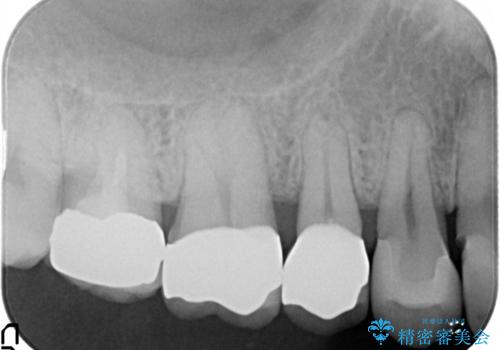

- 定期検診にて不良補綴物、及び虫歯を認めオールセラミッククラウンにて治療を行いました。

右上第二小臼歯はカリエス除去中に露髄を認め、部分的断髄法にて歯髄を保存しております。